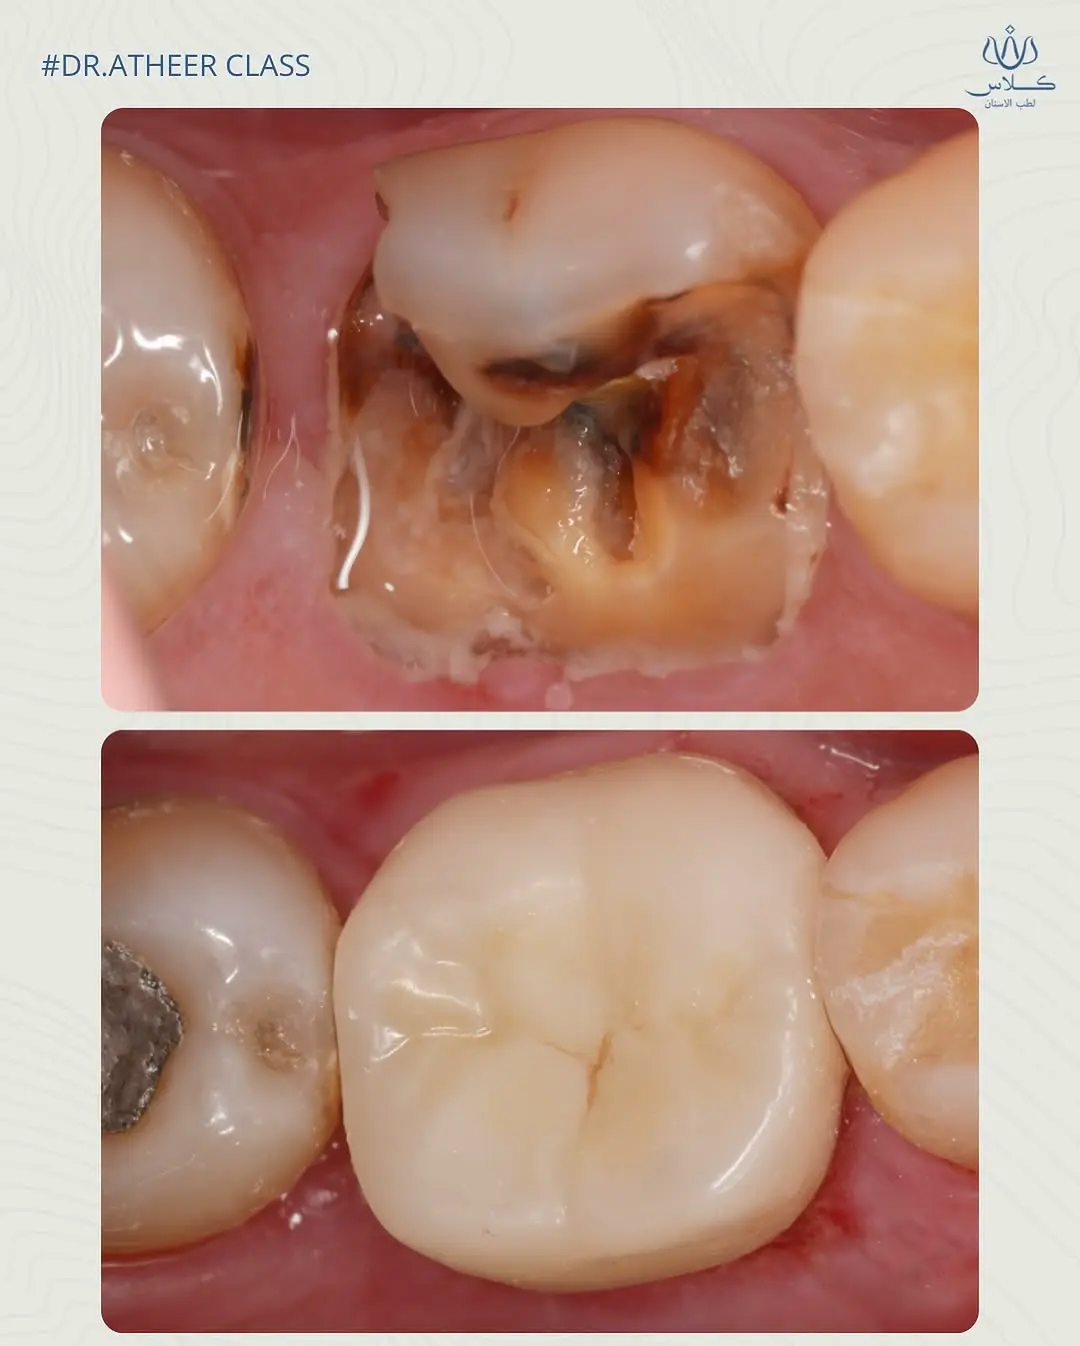

نتائج حالات د. اثير عدنان

قبل

بعد